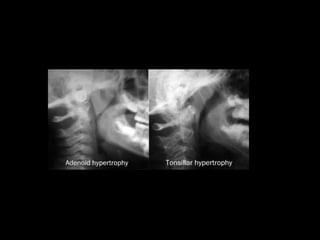

AMIĐAN QUÁ PHÁT BÍT TẮC MẠN TÍNH

(CHRONIC OBSTRUCTIVE TONSILLAR

HYPERTROPHY)

Sinh lý bệnh của amiđan quá phát ở trẻ em

Sinh lý bệnh của quá phát A có 2 quá

trình:

Quá phát và bít tắc đường thở trên (Airway

Obstruction).

Quá phát và ảnh hưởng sự tăng trưởng sọ

mặt (Craniofacial Growth).

Lâm sàng và đánh giá amiđan quá phát bít tắc

a.Đánh giá mức độ tắc nghẽn đường thở trên

Ngủ ngáy và ngưng thở lúc ngủ ở trẻ em.

Đêm ngủ: thở miệng, ngáy, hay thức giấc.

Giấc ngủ không say, đái dầm, ác mộng

Rối loạn phát âm, ảnh hưởng đến sự tăng

trưởng của trẻ, thành tích học tập kém.

b.Đánh giá ảnh hưỡng sự tăng trưởng sọ mặt

c.Đánh giá mức độ quá phát amiđan

Dựa vào mức độ thu hẹp của eo họng.

Phân độ quá phát amiđan từ độ I đến độ IV

Theo Brodsky, Leove và Stanievich